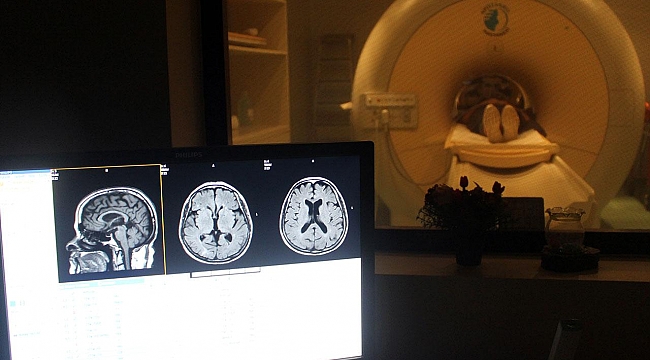

Harmancı, çalışmalarının merkezi sinir sisteminin en yaygın tümörlerinden biri olan "glioma" üzerine olduğunu belirterek, "Burada sorduğumuz soru, 'Glioma tümör hücreleri elektriksel olarak aktif mi? Yani, nöron özellikleri taşıyor mu?' sorusuydu. Bunun için de çok yeni olan bir yaklaşım uyguladık." dedi.

"Bu profilleme sonucunda tek bir hücrenin görüntüsü, yani morfolojisi, elektriksel aktivitesi ve içindeki genlerin ne kadar aktif olduğu bilgisine ulaştık. Bu profilleme sonucunda elimizde çok büyük bir data oluştu. Bu büyük datayı anlamlandırmak için beyin tümörlerine özel çeşitli algoritmalar, programlar geliştirdik. Bu programlar ve algoritmalar sayesinde bu tümör hücrelerinin bir kısmının hem glia hem de nöron özelliğine sahip olduğunu gördük."